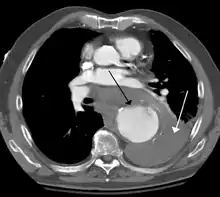

Thoracic aortic aneurysm

A thoracic aortic aneurysm is an aortic aneurysm that presents primarily in the thorax.

A thoracic aortic aneurysm is the "ballooning" of the upper aspect of the aorta, above the diaphragm. Untreated or unrecognized they can be fatal due to dissection or "popping" of the aneurysm leading to nearly instant death. Thoracic aneurysms are less common than an abdominal aortic aneurysm.[2] However, a syphilitic aneurysm is more likely to be a thoracic aortic aneurysm than an abdominal aortic aneurysm. This condition is commonly treated via a specialized multidisciplinary approach with both vascular surgeons and cardiac surgeons.

The principal causes of death due to thoracic aneurysmal disease are dissection and rupture. Once rupture occurs, the mortality rate is 50–80%. Most deaths in patients with Marfan syndrome are the result of aortic disease.